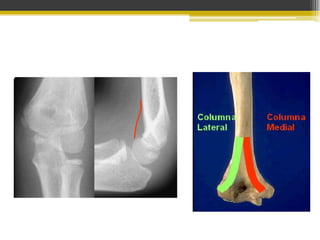

Fracturas distales del húmero

• Afectan a las metáfisis pueden o no extenderse a

la superficie articular.

Fracturas intraarticulares

 Columna simple: Cóndilo medial y

lateral

 Dos columnas: Intercondíliea en T y Y

Fracturas Intraarticulares

Fracturas en T o Y

• Mediana edad

• Fuerza axial

• Traumatismo directo en codo flexionado en 90

grados.

Clasificación Ao

• Tipo I: Fx bicondílea sin conminución

• Tipo II: Fx bicondílea con conminución

articular

• Tipo III: Fx bicondílea con conminución

articular y en columnas óseas supracondíleas.